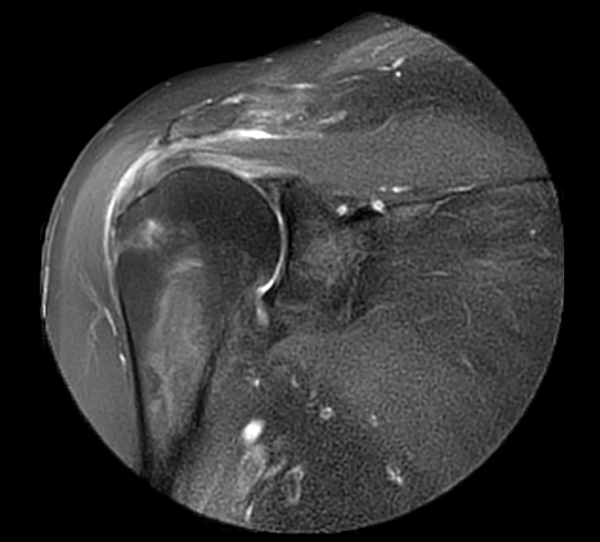

Coronal MultiVane XD - PDw SPAIR